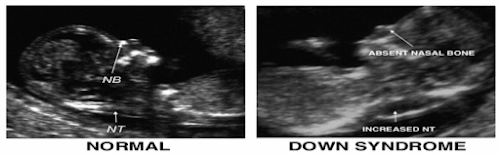

1. Nuchal Scan, yaitu pemeriksaan cairan dibelakang leher dengan menggunakan USG yang dilakukan bersamaan skrining kelainan anatomi janin trimester 1 yang hanya dapat dilakukan pada periode kehamilan 11-14 minggu. Pemeriksaan ini memiliki kemampuan deteksi 70 – 80%.